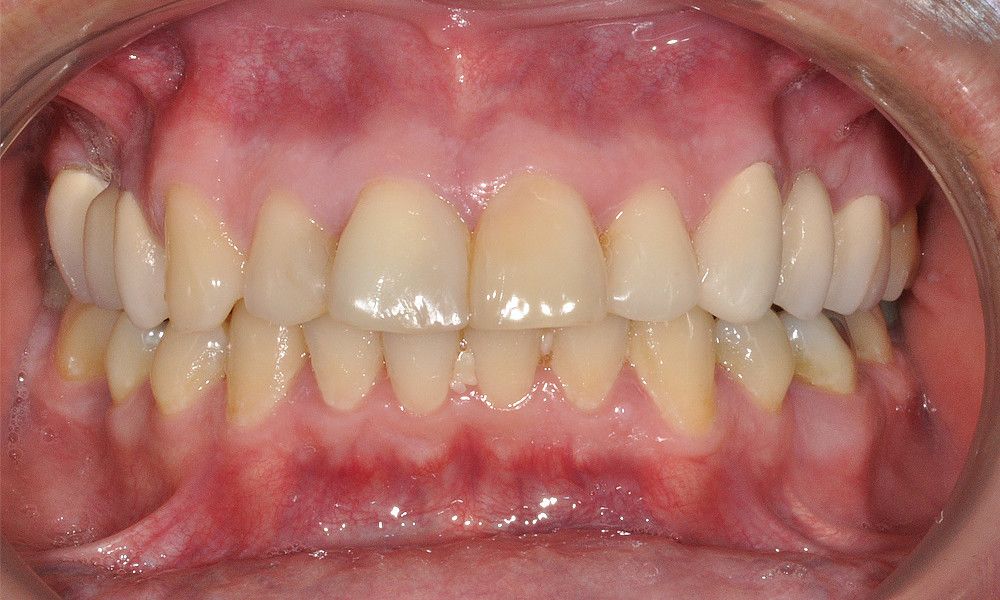

El estudio imagenológico evidencia una pérdida ósea severa en altitud y grosor, situación que complejiza la colocación de un implante. Se analizan alternativas de tratamiento y se opta por una vestibuloplastía mediante autoinjerto conectivo de mucosa palatina que se reposiciona sobre la zona del defecto óseo. Además se realiza retratamiento de ambas PFP, ahora en zirconia, por motivos estéticos y oclusales. Se realizan controles posteriores para evaluar la respuesta gingival a la vestibuloplastía.

Discusión: La vestibuloplastía se indica para el aumento de la cresta alveolar como soporte de prótesis. En este procedimiento dicha técnica sólo resuelve motivos estéticos. Se sugiere la técnica de preservación alveolar para evitar el colapso óseo posterior a extracción dentaria.